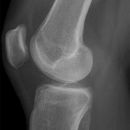

Kniegelenk seitlich

Patient in Seitenlage, Bein mit der Außenseite aufliegend, Knie leicht gebeugt, OSG mit Keil unterpolstern, so dass der Unterschenkel horizontal und parallel zum Film verläuft, Patella senkrecht , das gesunde Bein verläuft gesteckt dahinter.

Senkrecht auf Gelenkspalt und Filmmitte.

Ergussaufnahme: mit seitlich angestellter Kassette und horizontalem Strahlengang.

Deckungsgleiche Darstellung der Femurkondylen. Freier Durchblick durch das Femoropatellargelenk.